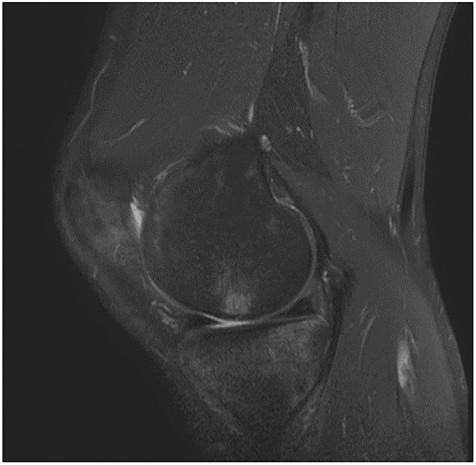

A 55-year-old male patient with a history of knee pain and difficulty with weight-bearing activities on the right side underwent arthroscopic repair of a large cartilage defect in his knee with MCA derived from his own knee cartilage (Figs 1, 2).